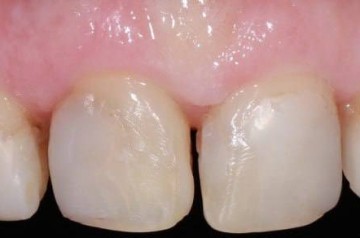

Установка коронки из диоксида циркония

Пациент, 42 года, обратился с жалобами на эстетические проблемы. Для улучшения внешнего вида его верхней челюсти были установлены коронки из диоксида циркония, которые отличаются повышенным гарантийным сроком службы. Подробнее о материале и его свойствах вы можете узнать на персональной консультации.